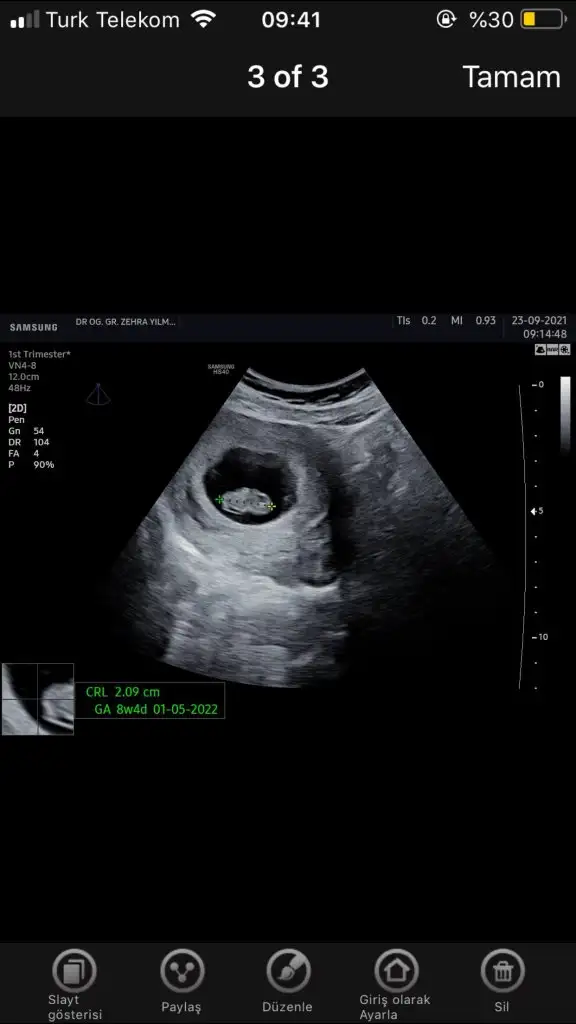

Ramzi teorisine göre cinsiyet tahmini yapacagim ilk ultrasyon resminizi atin bakiyim. Eger cinsiyetiniz belliyse hic söylemeeyin bakalm dogru tahmin edebilecekmiyim daha dogrusu ramzi teorisi hakli cikacak mi?

Ramzi teorisine göre;

Teoriye göre, kromozomların farklı yöne gitmesi ile plasentanın hangi durumda olduğu belirlenir. Yani plasentanın bulunduğu konum bebeğin cinsiyetini vermektedir. Plasenta rahmin sağında ise erkek, solunda ise kız bebek olacağı anlamına gelir.